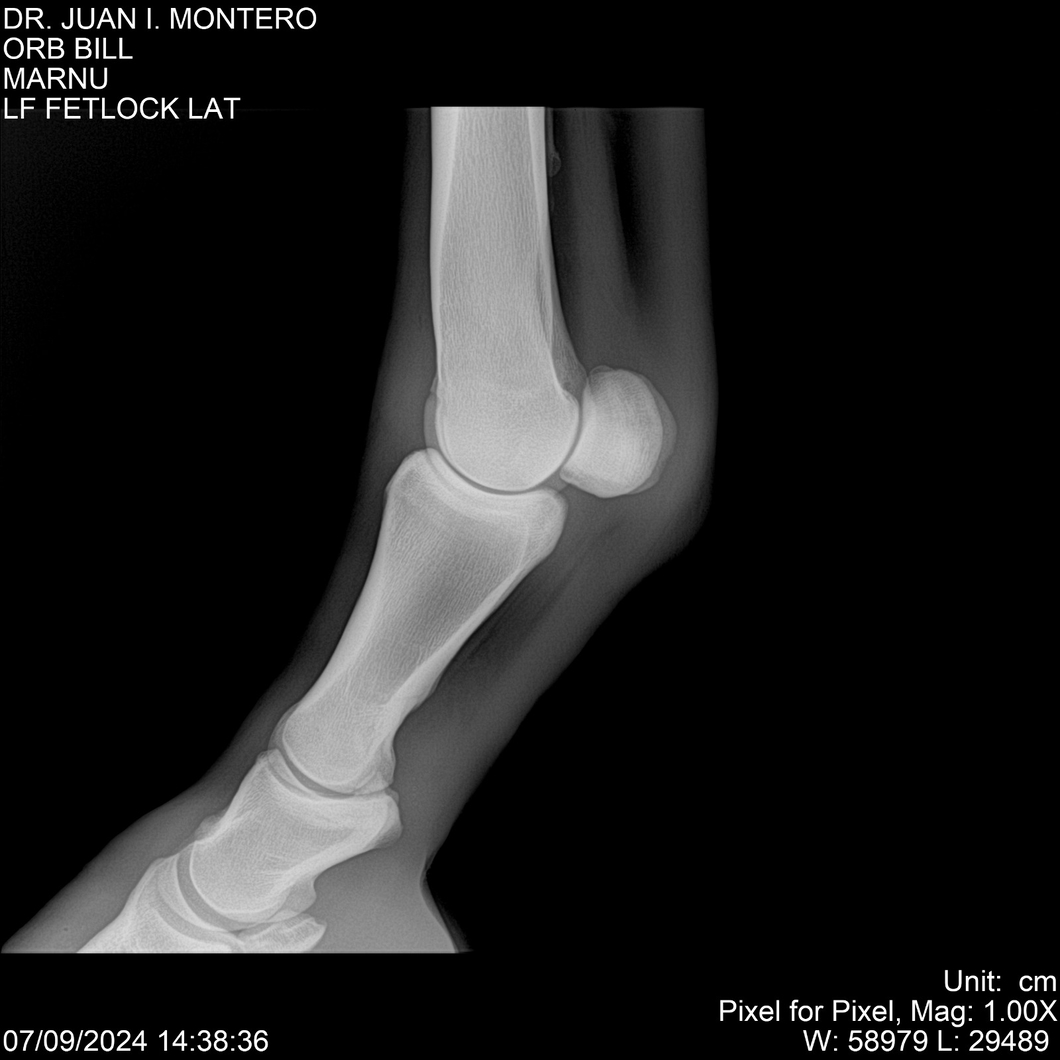

LOTE 7, ORB BILL 🔥 🔥 🔥 Lote Anterior Volver al remate Lote Siguiente Ficha Contacto Montevideo - Ficha del Lote Identificador: #282523 Categoría: Yeguarizos Montevideo - 83 Visualizaciones ClicData Contacto Empresa: Abelenda N. R., Walter Hugo Nombre*: Teléfono* : E-mail* : Mensaje Enviar Registrese gratis Este contenido Exclusivo está disponible sólo para usuarios registrados Ingresar